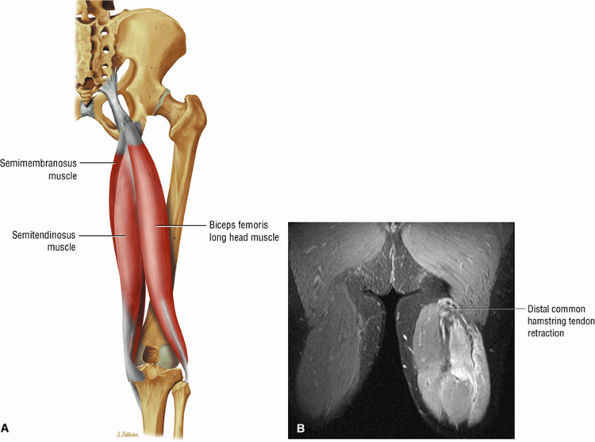

FIGURE 3.25 ● BICEPS FEMORIS The biceps femoris extends the thigh and flexes the leg in external rotation of the tibia, contributing to lateral stability of the knee. The muscles of the hamstring group (biceps femoris, semimembranosus, and semitendinosus), except for the short head of the biceps femoris, all cross the hip and the knee joint. Musculotendinous junctions extend the entire length of the muscle and serve as potential sites for strains. The short head is innervated by the peroneal branch of the sciatic nerve; the other hamstring muscles derive innervation from the tibial branch of the sciatic nerve.

FIGURE 3.26 ● SEMIMEMBRANOSUS The semimembranosus extends the thigh and flexes the leg. It is part of the hamstring muscle group (biceps femoris, semimembranosus, and semitendinosus) in the posterior thigh. Except for the short head of the biceps, the origins of the hamstring tendons are from the ischial tuberosity and are involved in ischial avulsion fractures in the young athlete.

FIGURE 3.27 ● SEMITENDINOSUS The semitendinosus, which is part of the hamstring muscle group, extends the thigh and flexes the leg. It may be used for anterior cruciate ligament reconstructions, posterolateral knee reconstructions, and tenodesis for patellar subluxation. It is the most posteromedial tendon on axial knee images at the joint line. Hip hyperflexion and simultaneous knee extension is a mechanism of injury for proximal hamstring injuries in adults and apophyseal avulsions in young skeletally immature athletes.

|